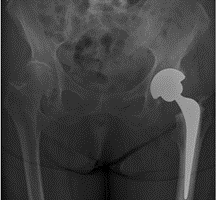

Du får taget røntgenbillede af din nye hofte

Du vil inden udskrivelse få taget et røntgenbillede af din hofte.

Fakta om hofteprotesen

Hofteprotesen består af 2 dele

- En del, som erstatter hofteskålen

- En del, som erstatter lårbenshovedet.

Hofteskålen består af en metalskal samt en plastikdel, der udgør sliddelen i hofteskålen. Protesen i lårbenet er af metal.

Hos patienter med stærke knogler bruger vi en protese med en ru overflade, som knoglen kan vokse sammen med.

Ved patienter med lidt svagere knogler, fx ældre patienter, sætter vi protesen fast med knoglecement, der binder som lim.

Den knoglecement, vi bruger, er af et fabrikat, der har været brugt i mere end 30 år uden problemer.